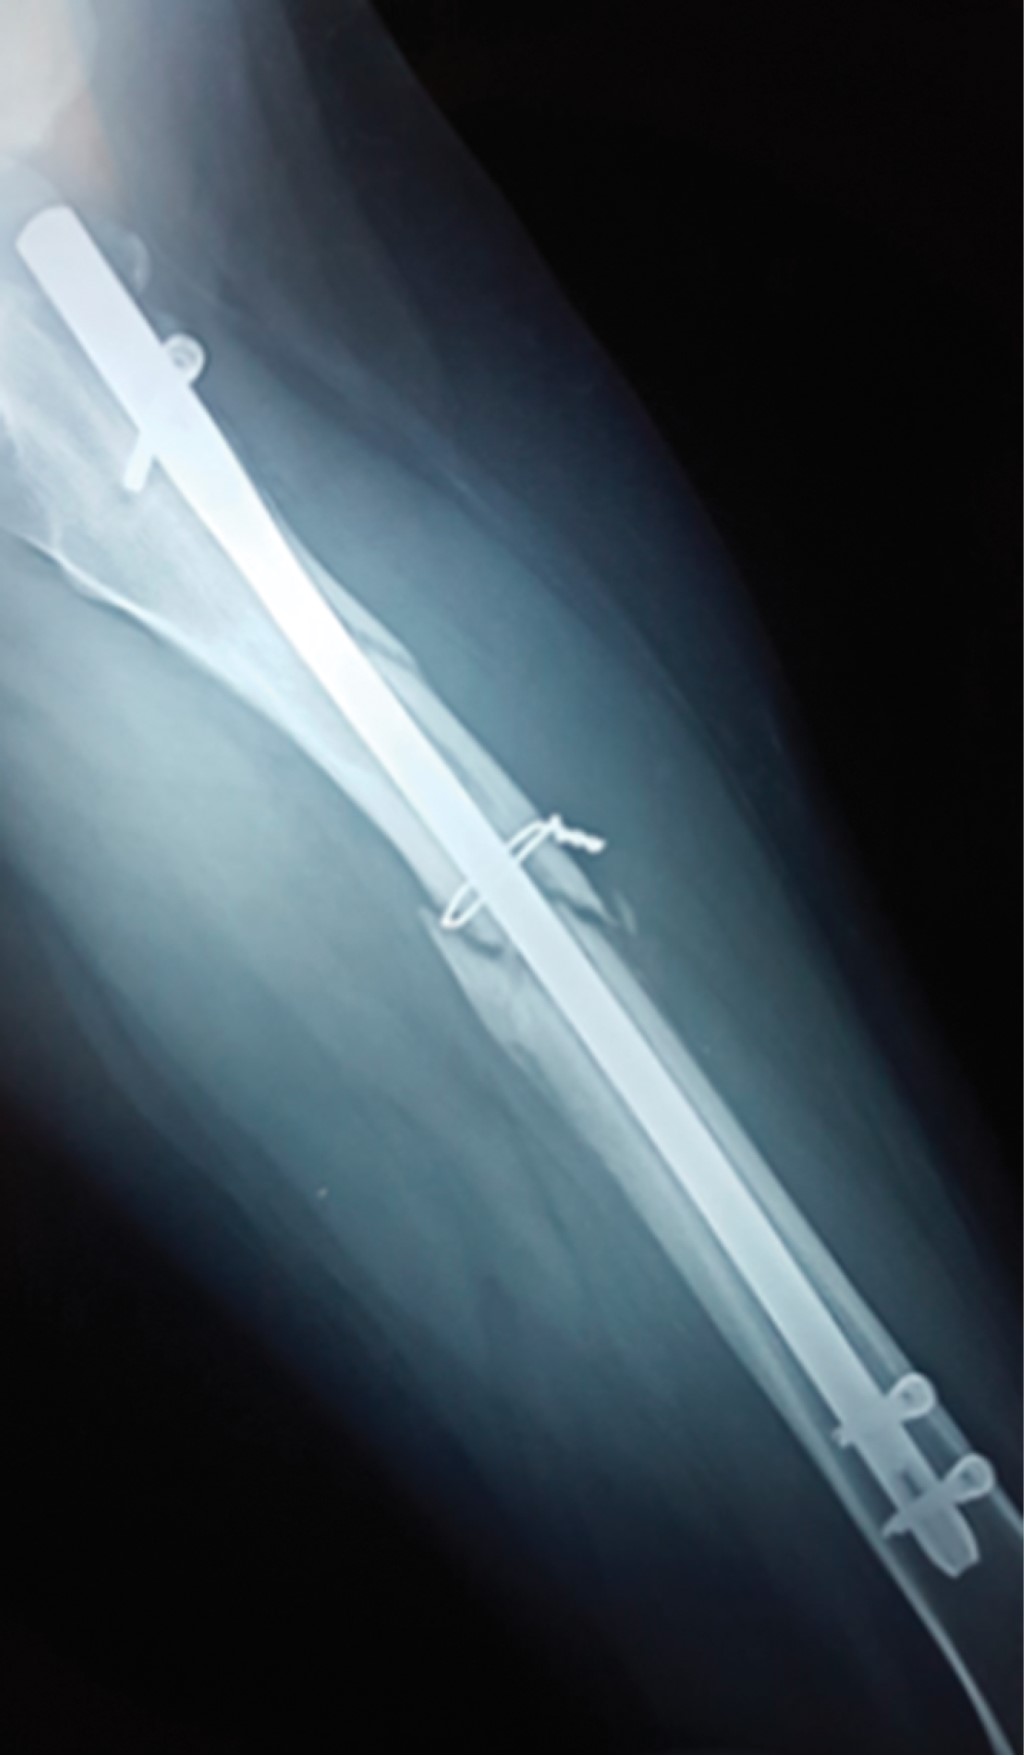

Pseudoarthrosis is a complication that poses a challenge for the orthopedist. If is associated with bone loss, a salvage surgery is indicated. There is no protocol for treatment for pseudoarthrosis with a "critical defect". The induced membrane technique, distraction osteogenesis, among others, has been described; however, the long time and elevated costs involved have opened a new landscape on the research of new protocols. The "diamond concept" which is not only based of improving biomechanics, but also introduces biological stimulation as a pillar of treatment, was recently introduced. We present the case of a 16-year-old female patient with a femoral shaft fracture after a traffic accident, treated initially with a centromedullar blocked nailing that progresses to pseudoarthrosis, presenting a 5 cm bone loss. Treatment consisted of removing the centromedullar blocked nail, resection of the nonviable bone segment, osteosynthesis with another centromedullar blocked nailing, placement a 7 cm diaphyseal allograft, platelet-rich plasma (PRP), matrix allograft, and bone chips, thus achieving radiographic and clinical consolidation; restoring limb function in a shorter time, considering the PRP as the main orthobiological element in this case.

Figure 2